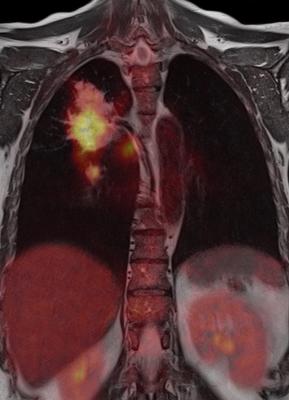

November 7, 2014 — Lung Cancer Awareness Month this year is different and may be the most significant in history. By Nov. 10, Medicare must rule on coverage for computed tomography (CT) lung cancer screening – the first and only test proven to reduce lung cancer deaths.

CT lung cancer screening works as well in people age 65 and over as it does in those 50-64. It is cost effective in Medicare and privately insured patients. There is no undue or lasting anxiety from this screening.

The United States Preventive Services Task Force (USPSTF) recommended (with a Grade of “B”) CT lung cancer screening of adults aged 55-80 who have a 30 pack-year smoking history and currently smoke or have quit within the past 15 years. The Affordable Care Act (ACA) requires private insurers to cover exams that receive a USPSTF grade of “B” or higher. The ACA does not specify that Medicare beneficiaries receive full coverage for these services.